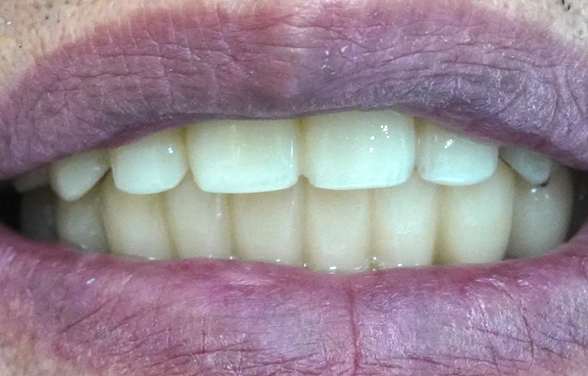

전체 임플란트, 단순히 치아가 생기는

것뿐만 아니라 예뻐져야 합니다.